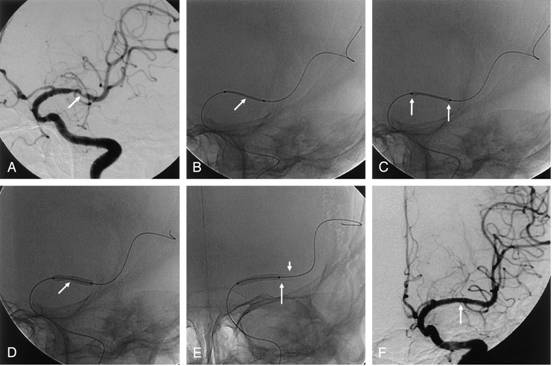

中部腦動脈狹窄,翼展支架置入: